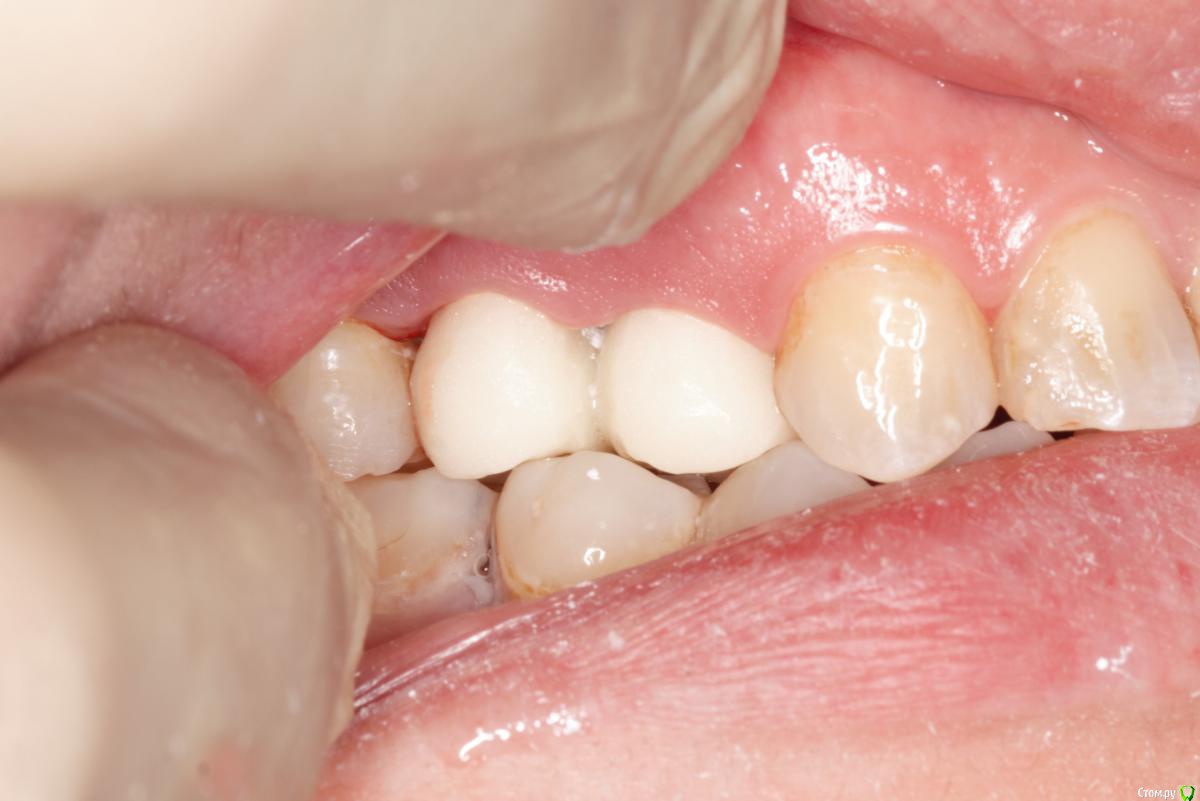

skeettrap Опубликовано 5 июля, 2016 Поделиться Опубликовано 5 июля, 2016 Стандартная ситуация : коллега попросила сделать родственнице (мужа) за неделю - во время краткосрочного визита из Израиля.Исходная ситуация 14,15 сильно разрушены с временными пломбами и наплывшей десной(фото не сделал).На первом этапе сделаны культевые вкладки прямым методом (десну подрезал бором). Постановка вкладок на следующий день, изготовление временных коронок, снятие слепков. Через 2 дня - фиксация. Ссылка на комментарий